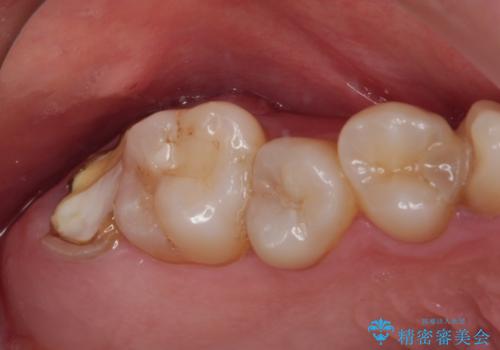

放置したむし歯 抜歯後にインプラントで補綴治療